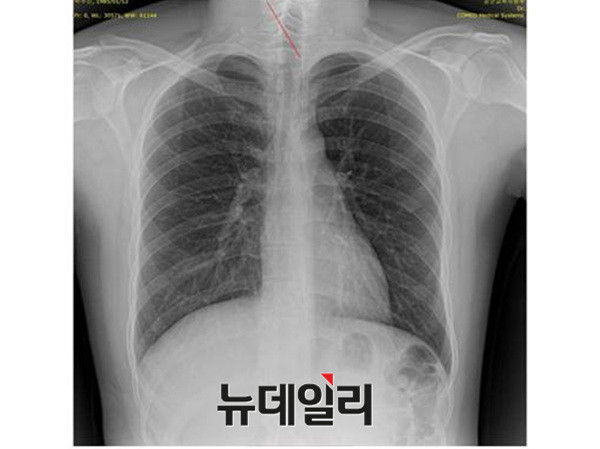

반면 지난해 12월부터 시작된 양승오 박사 등 시민 7명에 대한 공직선거법 위한 공판을 통해 새롭게 밝혀진, 박주신씨의 ‘공군훈련소 입소 당시 엑스레이’(촬영일자 2011년 8월 30일, 이하 공군 엑스레이)와, 주신씨가 ‘비자발급을 위해 촬영한 세브란스병원 엑스레이’(촬영일자 2014년 7월 31일, 이하 비자발급용 엑스레이)는 각각 박주신씨 본인의 신체를 촬영한 것으로 받아들여지고 있다.

- ▲ 박주신씨가 지난해 7월 비자발급을 위해 촬영한 엑스레이. ⓒ 뉴데일리DB

이들 세 개의 엑스레이는 모두 박주신씨의 신체를 촬영한 것으로 알려져 있기 때문에, 이들 엑스레이에 대한 판독결과 피사체를 동일인으로 볼 수 없는 유의미한 차이점이 발견된다면, 이는 박주신씨의 대리신검 혹은 영상자료 바꿔치기 의혹을 뒷받침하는 결정적 단서가 된다.

세계적 권위를 인정받은 영상의학 전문의인 양승오 박사(동남권원자력의학원 암센터 핵의학과 주임과장)와 치과의사 김우현씨 등 박주신씨 병역비리 의혹을 주장해 온 시민들은, 위에서 언급한 세 개의 엑스레이에 대한 비교 판독 결과, 이들 엑스레이를 같은 사람의 것으로 볼 수 없는 차이점을 발견하고 이를 재판부에 증거자료로 제출했다.

양승오 박사 : “언론을 통해 알려진 T2영상 신호강도에 따르면, 적색 조혈 골수와 황색 지방 골수가 불규칙하게 섞여 있는데, 이는 20대의 골수에서는 상당히 찾아보기 힘든 패턴이다.

골수는 적색의 조혈 골수와 황색의 지방 골수로 이뤄지는데, 나이가 들면서 황색의 지방 골수가 늘어나게 된다.

10~20 세 남성은 24.6%의 황색 지방 골수(yellow fatty marrow) 분포를 보이지만, 21~30세 남성은 33.5%, 31~40세 남성은 41.4%, 41~50세 남성은 47.6%의 황색 지방 골수 분포를 보인다.

이러한 연령대별 골수강도를 고려할 때, 박주신씨의 MRI 영상에 나타나는 골수강도는 최소 35세 이상에 가까운 상태다.

20대로서는 불가능한 골수강도라 할 수 있다. 만약 박주신씨가 정말 심한 ‘골초’라면, 골수의 변화가 가능하다. 그러나 박주신씨는 비흡연자로 알려져 있지 않은가.

이에 해당 MRI 영상은 박주신씨의 것이 아닐 가능성이 의학적으로 아주 높다.

참고로 연세대 발표 사진과 35세 남자의 척추영상 MRI 증례를 비교해 보면, 연세대 사진에서 흰색으로 나타나는 지방골수가 불규칙한 양상을 띠면서 증가돼 있다는 사실을 알 수 있다”

연세대 MRI 미스터리, 해외 전문의들의 의학적 소견“해당 요추 MRI는 36~40세 남성의 것”

연세대 세브란스 병원이 촬영한 박주신씨 허리 MRI 사진에 대한 의문은 해외 의학자 사이에서도 나오고 있다.[영상의학계의 석학]이라 불리는 ‘주세페 굴리엘미’ 박사는 박주신씨 MRI 사진 자료를 접한 뒤 다음과 같은 반응을 보였다.

“In regard to your question due to the BM aspect and the disc signal,

I believe that this lumbar MRI can be attributed to a male of 36-40 years old.골수양태와 추간판 신호에 근거해 답을 드리면, 해당 요추 MRI는 36~40세 남성의 것으로 볼 수 있다”

‘주세페 굴리엘미’(Giuseppe Guglielmi) 박사는, 유럽 근골격 방사선학회 골다공위원장으로, 이탈리아 Foggia 대학교 영상의학과(방사선학) 교수다.아시아근골격학회(AMS) 회원이자 태국 Chiang Mai 대학교 교수인 너트(Nutaya) 박사 역시, 비슷한 소견을 밝혔다.

“late 40 to 60 I guess.

Bone marrow of adult, disc bulge a little bit, mild flavum thickening, and considerable amount of visceral fat. Surprising that the retrolisthesis didn't cause pain.

40대 후반에서 60대로 추측된다.

성인의 골수, 디스크 약간 돌출. 인대가 두꺼워져 있고 상당한 양의 내장지방이 보인다. 척추전위증이 통증을 수반하지 않았다는 것이 놀랍다”

MRI 촬영 당시 박주신씨의 나이는 27세. 그러나 MRI 영상의 주인은 약 40~60대로 추정된다는 것이 해당분야 전문가들의 공통 소견이다.전문가들의 견해를 종합하면, 박주신씨는 일반인보다 최소 10~20년 이상을 앞서 살고 있다는 결과가 나온다.